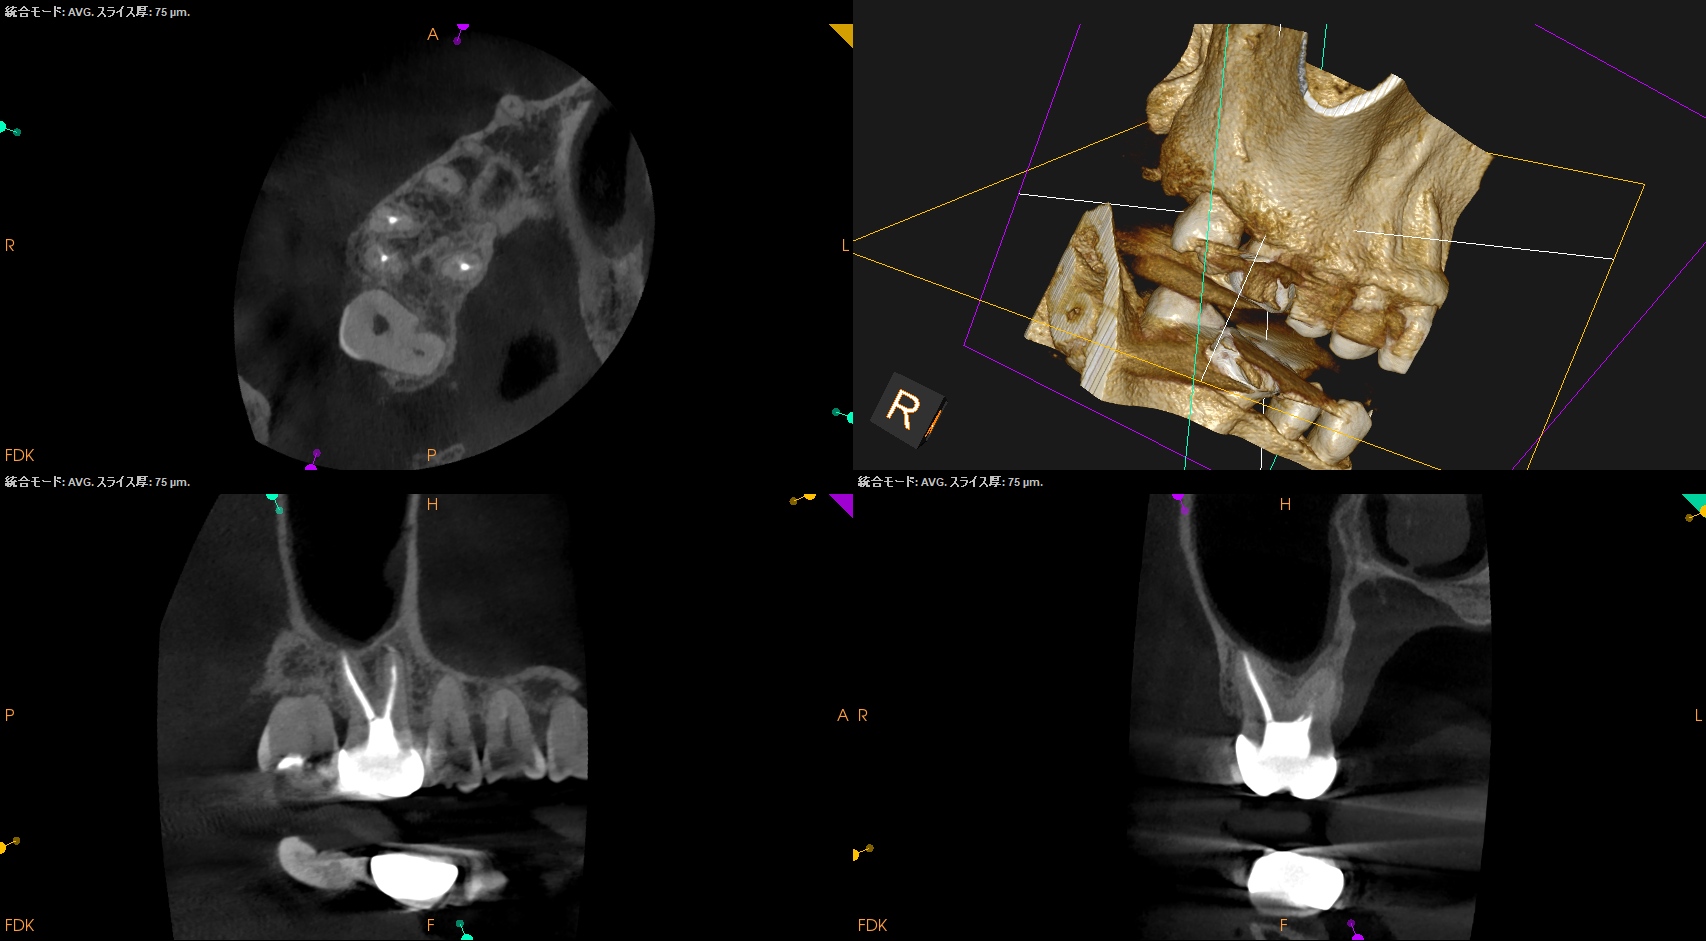

PA, CBCTも撮影した。

B

初診時と比較した。

はみ出たBC sealerが消失して歯槽骨と置き換わっている

という臨床的事実だ。

BC sealerは組織液と反応して生体親和性の高いハイドロキシアパタイトを生成すると信じられており、それは自家骨に置き換わると信じらている。

炎症性滲出液や嚢胞の存在によってはみ出たシーラーは吸収されると信じられているようだ。

このケースではみ出たBC sealerが歯槽骨に置き換わったのか?私にはわからない。

が、根尖病変が治癒し歯槽骨に置き換わったのは紛れもない事実だ。